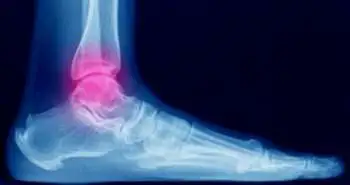

Ankle fracture-dislocation occurs more commonly in elderly diabetic females with poor functional outcomes.

Substantial injury to the bony and soft tissue structures of the ankle is known as fracture dislocation of the ankle. Only limited reporting of functional outcome of ankle fracture-dislocations have been studied so far. Hence, this retrospective chart review focused on distinguishing the functional outcome after open reduction internal fixation in ankle fractures with and without dislocation.

This review of surgically treated ankle fractures spanned over 3 years. The fracture type, demographic data, operative time and complications were noted. Thirty-three (28%) patients out of 118 patients eligible for analysis sustained a fracture-dislocation. The mean patient age was 46.6 years. Sixty-two patients, who had a follow-up of at least 12 months, were investigated for functional outcome using Foot and Ankle Outcome Score (FAOS). Median follow-up time was 37 months.

The demographic variables and FAOS were compared between ankle fractures with and without dislocation. The average age of patients sustaining a fracture-dislocation was higher (53 vs 44 years); with a greater percentage being female (72.7% vs 51.8%) and diabetic (24.2% vs 7.1%). Both groups witnessed similar wound complications. Generally, FAOS was poorer in the fracture-dislocation group; nonetheless only the pain subscale portrayed statistical significance (76 vs 92).

The researchers of this study concluded that at a median of just > 3-year follow-up, functional outcomes in fracture-dislocations were generally poorer and also, the pain subscale of FAOS was worse in a statistically significant fashion.